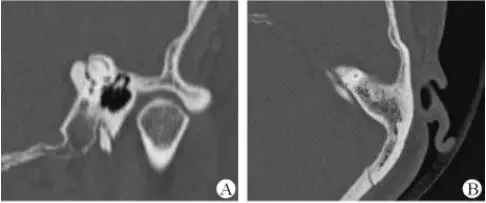

診斷及治療

醫(yī)生若懷疑此病將會安排內耳CT掃描。在大多數(shù)案例中,一旦此病被耳鼻喉科醫(yī)生或其它聽力健康專家確診,則可實行手術治療。外科手術風險包含聽力損失以及神經(jīng)損傷;重建及復原需內耳的治療以及大腦的重塑。